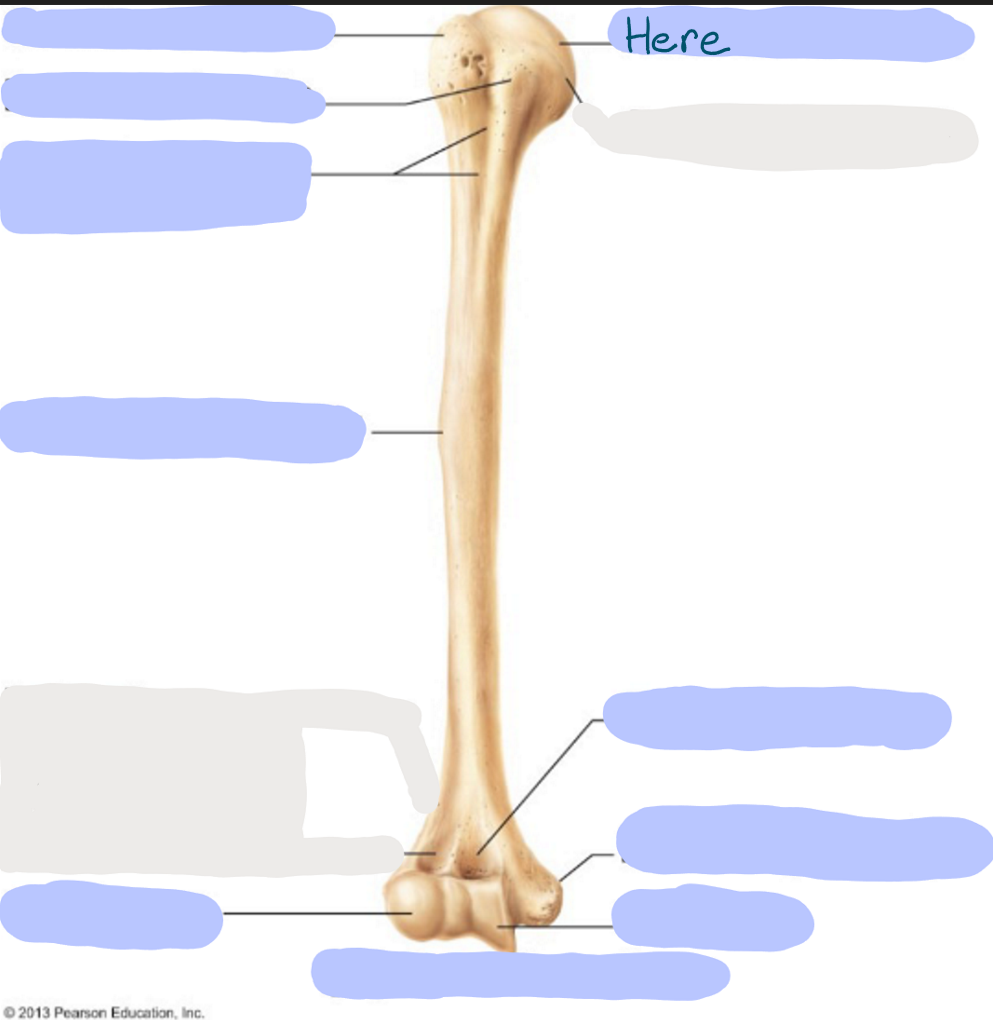

What is this picture of?

Anterior view of the Right Femur

What is here?

Where is the Neck of the Femur?

What is here?

Where is the Head of the Femur?

What is here?

Where is the Lesser Trochanter of the Femur?

What is here?

Where is the Lateral Epicondyle of the Femur?

What is here?

Where is the Medial Epicondyle of the Femur?